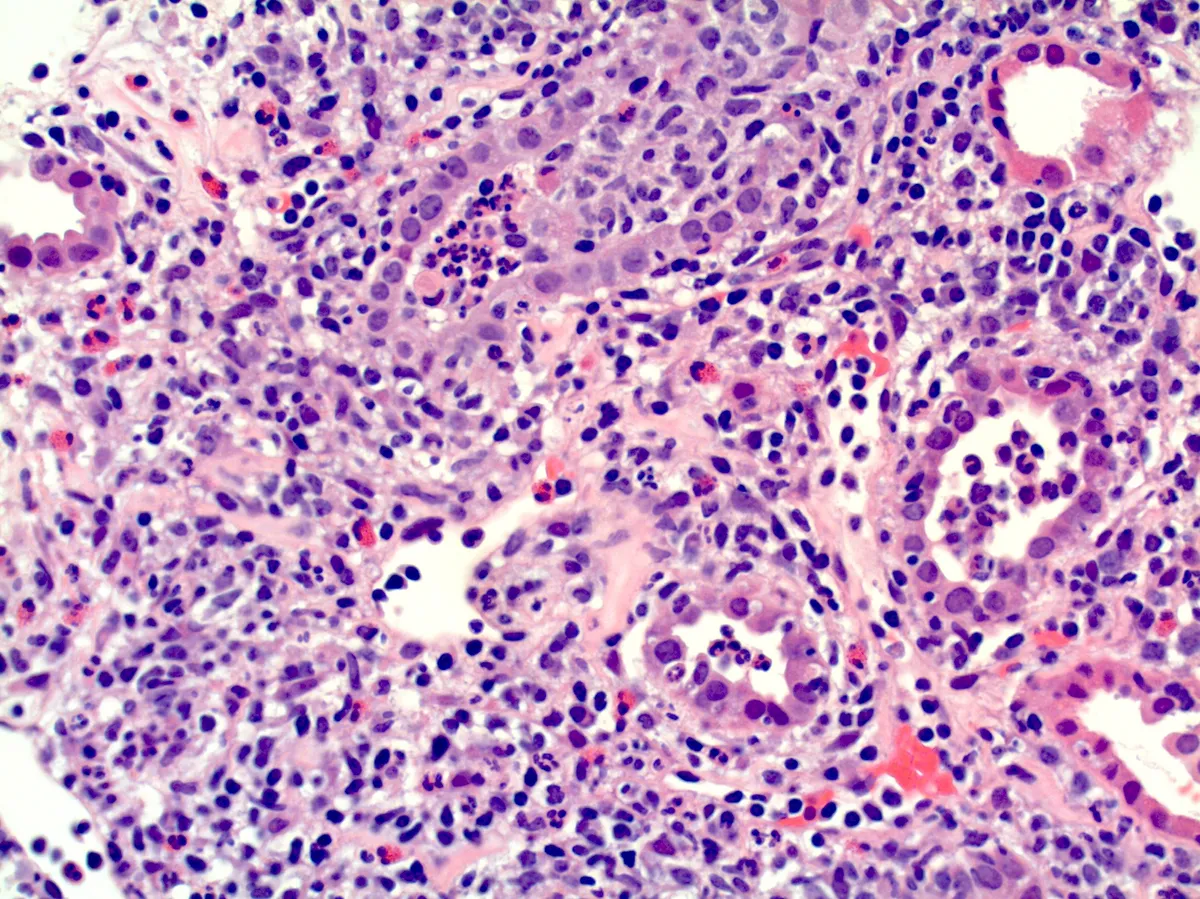

Meu paciente com NIgA tem proteinúria entre 0,5–1,0 g/dia, já está em iECA e iSGLT2: devo pensar em imunossupressão?

Proteinúria entre 0,5–1,0 g/dia na NIgA não é benigna e já se associa a maior risco de progressão renal. A evidência atual reforça <0,5 g/dia como alvo terapêutico, valorizando proteinúria cumulativa e tendência ao longo do tempo. Antes de pensar em imunossupressão, o foco deve ser otimização máxima da terapia de suporte e estratificação cuidadosa de risco.